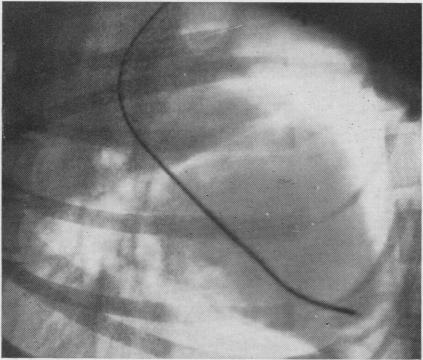

The use of the P wave for control of a pacemaker in heart block.

Thorax. 1960 Jun;15(2):177-80. doi: 10.1136/thx.15.2.177.